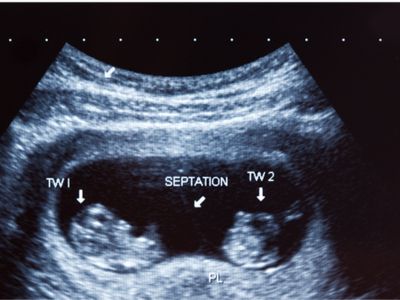

Anomaly Scan

Raaya Diagnostic Center offers specialized anomaly scan services for expectant mothers, typically performed between 18 to 22 weeks of pregnancy. This comprehensive ultrasound examination assesses fetal anatomy, including the development of organs, limbs, and other structures, to detect any potential abnormalities or congenital defects.

With our advanced ultrasound technology and experienced sonographers, Raaya Diagnostic Center ensures thorough and accurate evaluations during the anomaly scan. Our dedicated team provides support and reassurance to expectant parents, guiding them through the process with care and expertise. Contact us to schedule your appointment or to learn more about our obstetric sonography services.